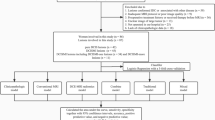

Eighty-six consecutive women with 86 DCIS lesions diagnosed by biopsy underwent UF-MRI including pre- and 18 post-contrast ultrafast scans (temporal resolution of 3 s/phase). The last phase of UF-MRI was used to perform 3D segmentation. The time point at 6 s after the aorta started to enhance was used to obtain subtracted images. From the 3D segmentation and subtracted images, enhancement, shape, and texture features were calculated and compared between low- and non-low-grade or upgrade DCIS lesions using univariate analysis. Feature selection by least absolute shrinkage and selection operator (LASSO) algorithm and k-fold cross-validation were performed to evaluate the diagnostic performance.

Surgical specimens revealed 16 low-grade DCIS lesions, 37 non-low-grade lesions and 33 upgrade DCIS lesions. In univariate analysis, five shape and seven texture features were significantly different between low- and non-low-grade lesions or upgrade DCIS lesions, whereas enhancement features were not. The six features including surface/volume ratio, irregularity, diff variance, uniformity, sum average, and variance were selected using LASSO algorism and the mean area under the receiver operating characteristic curve for training and validation folds were 0.88 and 0.88, respectively.